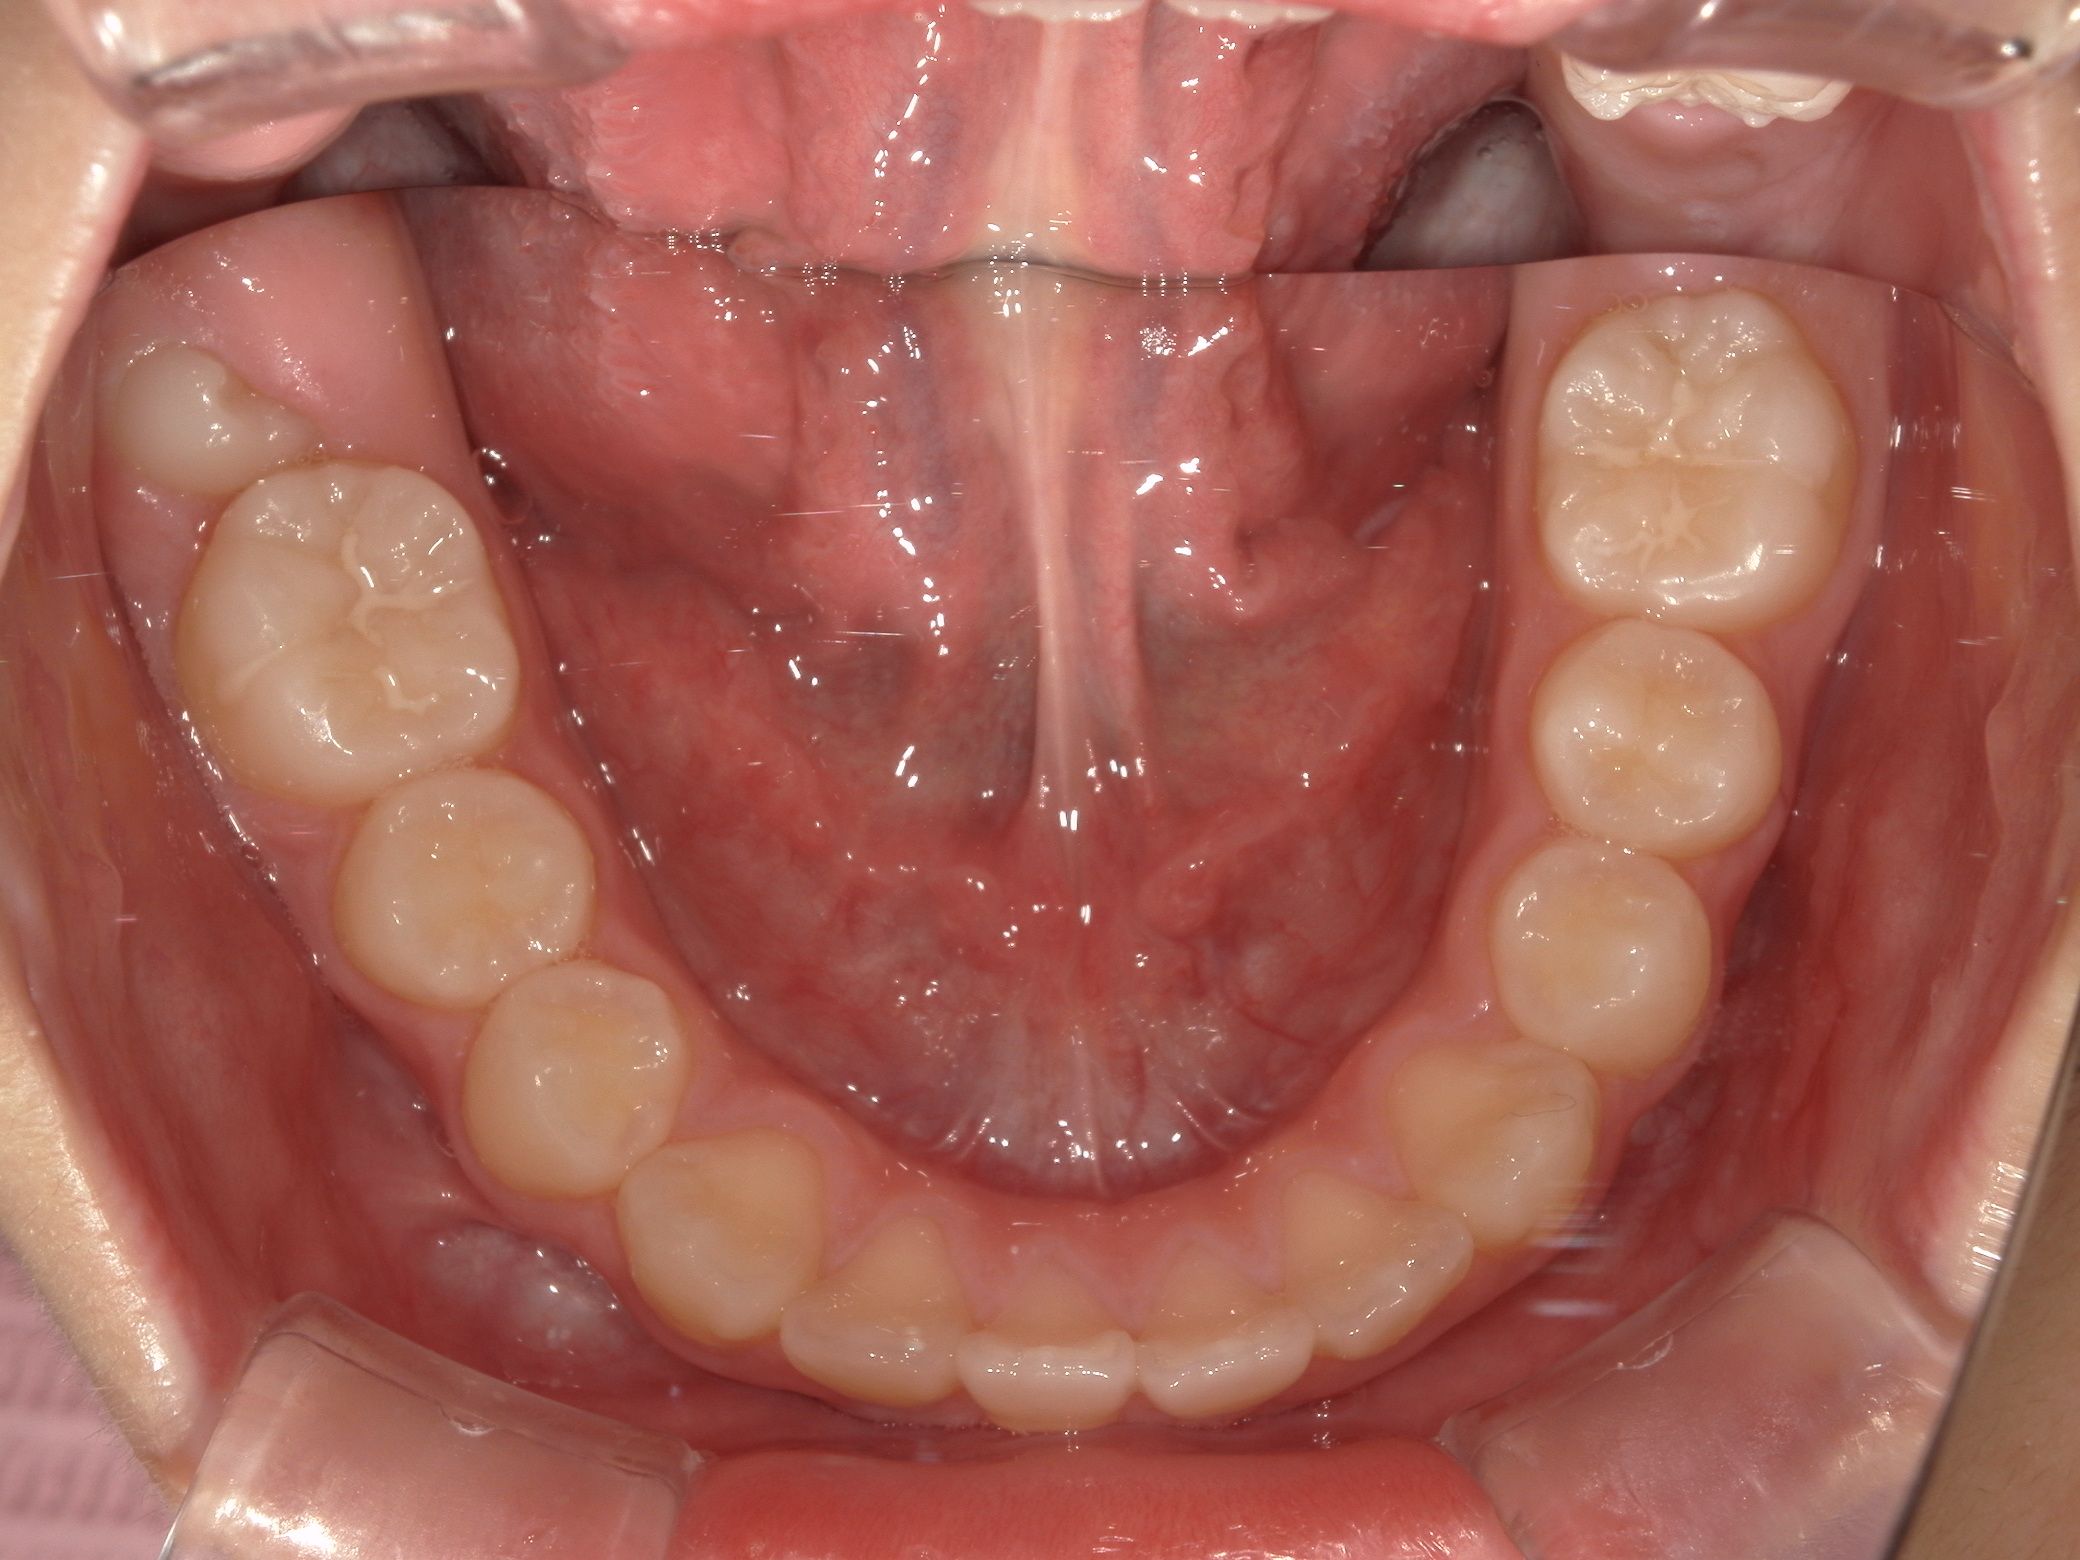

治療中 During treatment

上顎がバイオブロックにより広がり、すき間ができています